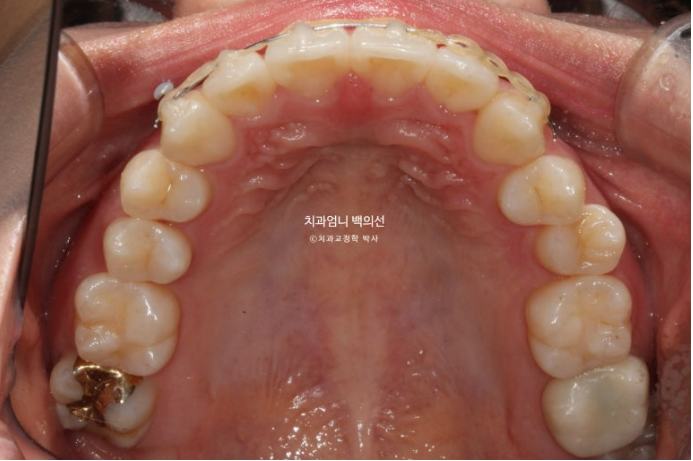

이제 전 후 비교해보겠습니다.

23.12~24.09

고무줄 사용으로 송곳니 교합관계도 개선되었습니다.

가지런한 앞니 배열과 철사 유지장치

주변치아에 비해 유난히 커보였던 앞니는 높낮이와 배열이 맞아지니 이제는 커보이지 않습니다.

치간삭제를 동반하여 앞니를 배열했기 때문에 처음에 비해 돌출되지 않고 유지되었고 원래 예뻤던 입매도 잘 유지가 되었습니다.